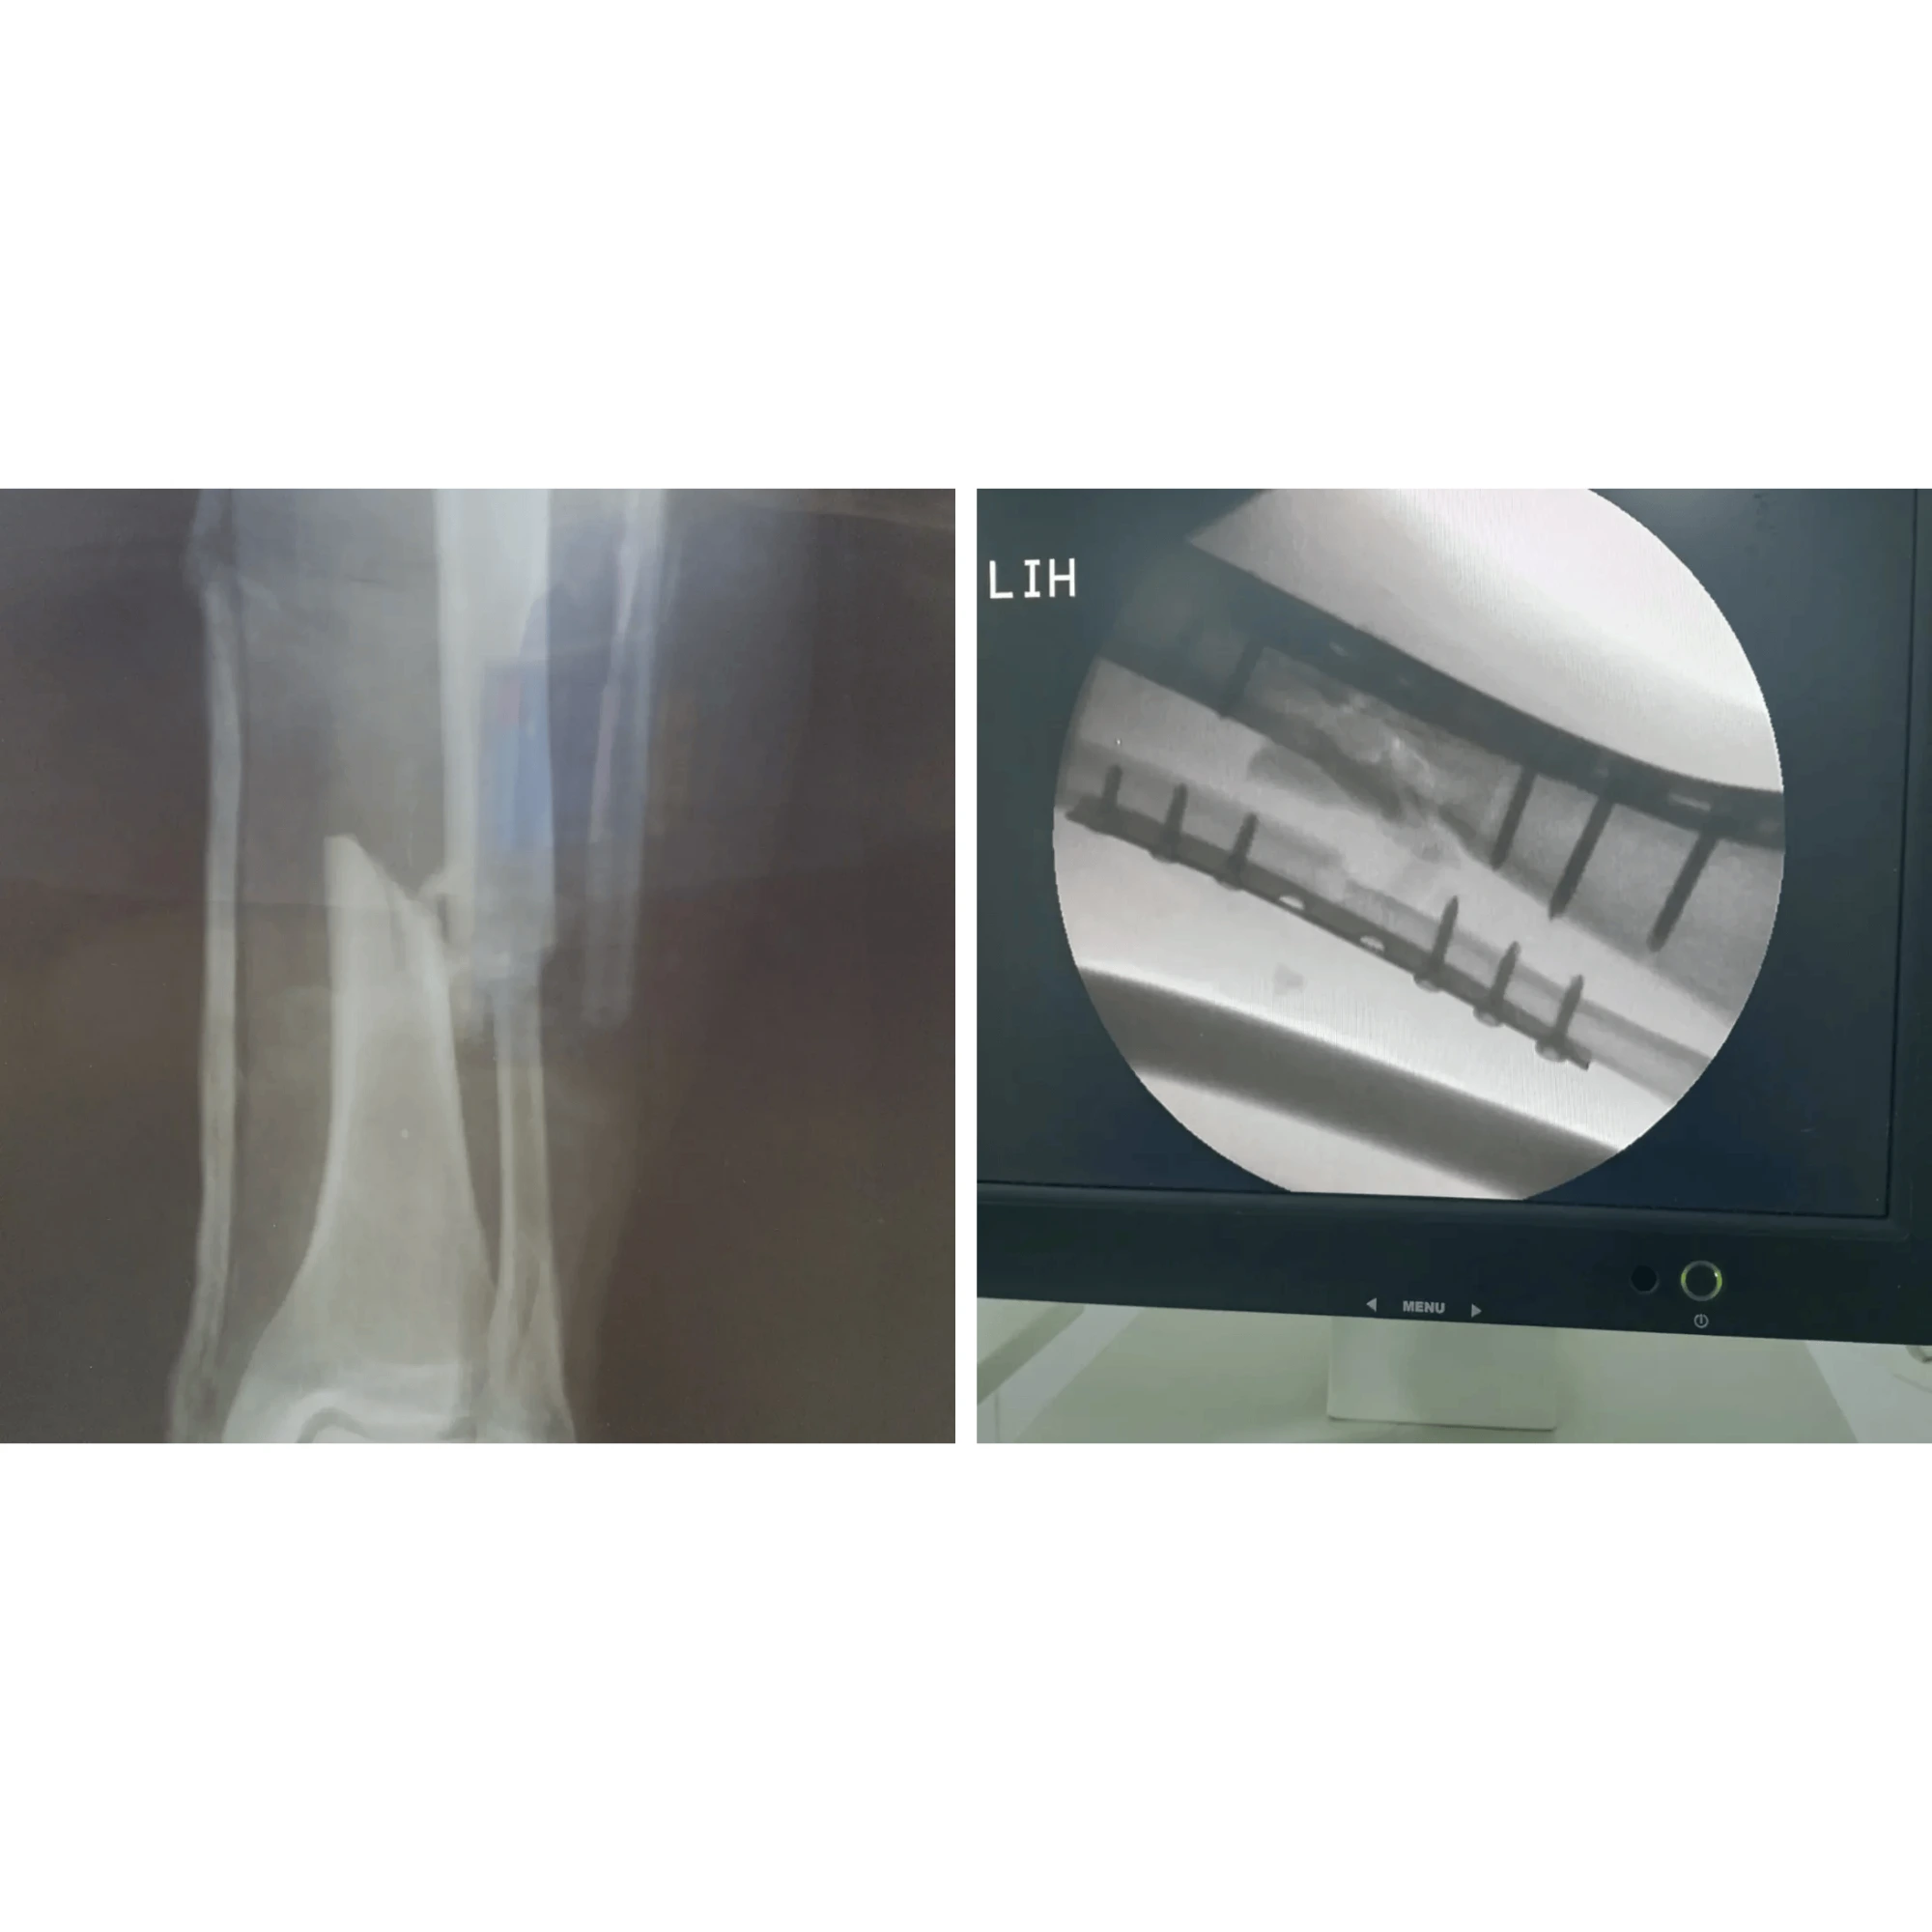

Mürəkkəb sınıqların və oynaq xəstəliklərinin müasir metodlarla bərpasının vizual nəticələri. Pasientlərimizin itirilmiş hərəkət funksiyalarının geri qazanılması bizim ən böyük uğurumuzdur.

Hər bir müalicə prosesi yüksək dəqiqlik və müasir cərrahi standartlara əsaslanır. Bu bölmədə Op. Dr. Aqil Yusubovun əməliyyatxana fəaliyyəti, kliniki iş mühiti və tətbiq etdiyi innovativ metodlarla yaxından tanış ola bilərsiniz.